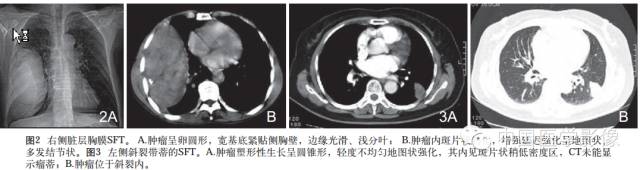

1.外形及囊变坏死:良性SFT一般为边界清晰的单发肿块无分叶或浅分叶,肿瘤大多呈实性,囊变坏死区较小。恶性SFT一般为囊实性或囊性为主肿块呈分叶状坏死范围广泛。

2.密度或信号特点:肿瘤实性部分CT表现为软组织密度,囊变坏死区呈低密度。位于胸腔的SFT尽管体积巨大,但密度相对均匀,坏死少见且范围多较小。良性肿瘤坏死少见,恶性肿瘤不规则坏死区相对多见。腹部SFT都有不同程度的坏死囊变和钙化。MRI除了能够提供明确肿瘤的确切部位及累及范围外,对于明确肿瘤的组成成分具有重要价值。MR信号改变与肿瘤的组织学特征密切相关,其内成熟的纤维组织在T1WIT2WI序列上均呈低信号,而肿瘤细胞及血管聚集区则呈等T1长T2信号,因此T1WI一般为等信号或低信号T2WI多为混杂信号。文献认为T2WI低信号对于本病诊断具有重要价值。

4.铸型生长:由于良性SFT生长缓慢,发生于胸膜腔的孤立性纤维性肿瘤常呈斜圆锥体状,铸型镶嵌于肋膈角。此征象的出现与病灶生长时间及部位密切相关。

6.增强扫描:SFT为富血供肿瘤,增强扫描呈肿瘤实性部分呈地图样明显强化、延迟扫描进一步强化是SFT的主要特征。病灶实性部分显著强化与镜下血管外皮瘤样分布区及细胞密集区有关,而肿瘤内部坏死囊变区不强化。此外,细胞稀疏区与胶原纤维束玻璃样变区域强化相对较弱,因此形成地图样不均匀强化表现。持续性强化的模式可能与病灶内胶原纤维缓慢强化有关,还可能与黏液样变及细胞疏松排列导致细胞外间隙扩大对比剂在细胞外间隙内进行性聚集有关,因此动态扫描对于本病的诊断具有重要价值。